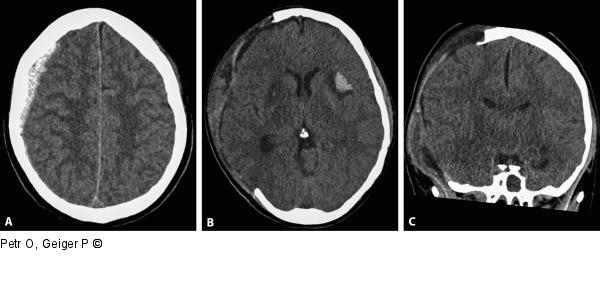

Abbildung 2a-c: Akutes Subduralhämatom aSDH nach Skiunfall mit diffuser Hirnschwellung (A); Zustand nach Entlastungskraniektomie (B) zur Entlastung des überhöhten Hirndrucks durch Hirnschwellung. Die Temporobasis muss ausreichend entlastet sein, damit keine Herniation stattfinden kann (C). |

Abbildung 2a-c: Akutes Subduralhämatom

aSDH nach Skiunfall mit diffuser Hirnschwellung (A); Zustand nach Entlastungskraniektomie (B) zur Entlastung des überhöhten Hirndrucks durch Hirnschwellung. Die Temporobasis muss ausreichend entlastet sein, damit keine Herniation stattfinden kann (C). |